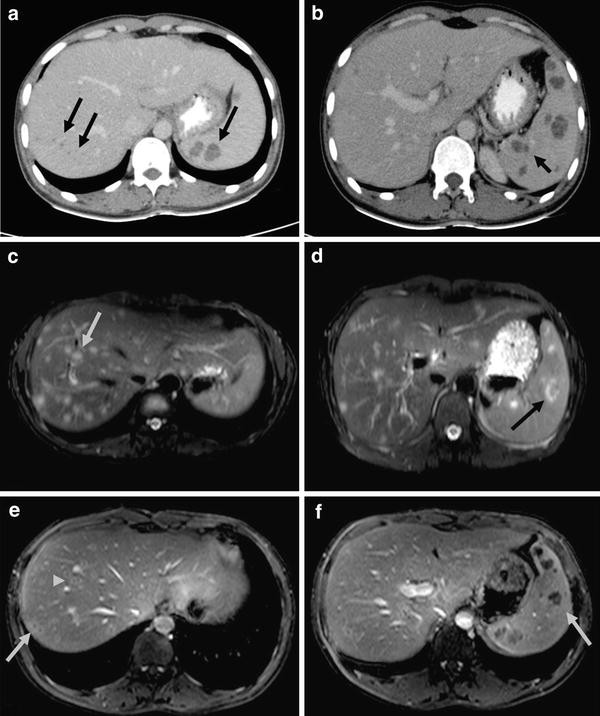

Liver Ct Scan Cost In India - Ct scan is an acronym for computerized tomography.